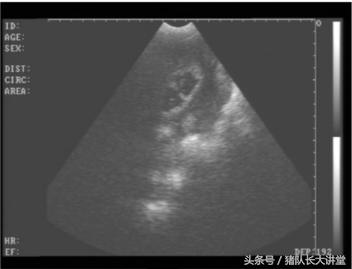

23天的B超图

2、这里只说下B超因为本人用的也比较多;

A、可以较为准确的测出是不是有小猪,具体使用办法,根据说明使用,大家也可以提出问题;关注,一般你检测有的就是有了,单是检测没有的时候应该多观察;